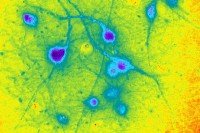

In the Lab

Seeing the Light: How Engineered Nerve Cells Might Curb Parkinson’s Disease

A new tool called optogenetics is revealing clues about the function of a promising experimental therapy derived from stem cells.

In the Lab

Researchers Fast-Forward Stem Cell Aging to Study Degenerative Diseases

A team of Memorial Sloan Kettering scientists has come up with an approach to make stem-cell-derived neurons rapidly age in a cell culture dish. The breakthrough could transform research into Parkinson’s and other late-onset diseases.